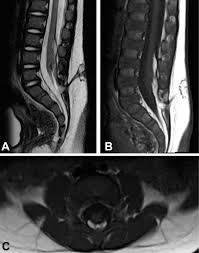

Tethered cord syndrome in adults indications. Tethered cord syndrome TCS is rare but no one knows exactly how prevalent it is because it commonly goes undiagnosed. Adult tethered cord is determined by an MRI which shows a low level of the conus medullaris below L2 and thickened filum terminale. Less qualifiers are acceptable with indirect imaging findings.

The adult presentation of tethered cord syndrome TCS is well recognized but continues to pose significant diagnostic and management challenges. The tethering effect was caused either by a split cord malformation a thick filum terminale a conus medullaris lipoma with extradural extension or various combinations of these mechanisms. Progressive sensory and motor deficits may affect the legs potentially resulting in numbness weakness or.

Indications techniques and long-term outcomes in. Adult tethered cord is determined by an MRI which shows a low level of the conus medullaris below L2 and thickened filum terminale. The occult tethered cord syndrome and surgical indication - PEDs Neuro Ortho UroGI Progressive Syringohydromelia Filum 2mm in axial section Derm ¾ clinical qualifiers mandatory for surgical indication. In adults symptoms are aggravated by trauma maneuvers associated with stretching of the spine flexion disc herniation and spinal stenosis. J Neurosurg Spine 42123-1312006. The tethering effect was caused either by a split cord malformation a thick filum terminale a conus medullaris lipoma with extradural extension or various combinations of these mechanisms. The authors performed a retrospective study of clinical outcomes after neurosurgical intervention in 60 adults with TCS. Of the 2515 patients 85 adults with a tethered cord syndrome formed the basis of this study. In the present study we analyzed the data of patients who presented with TCS in adulthood with the aim of studying the clinical spectrum and management strategies.